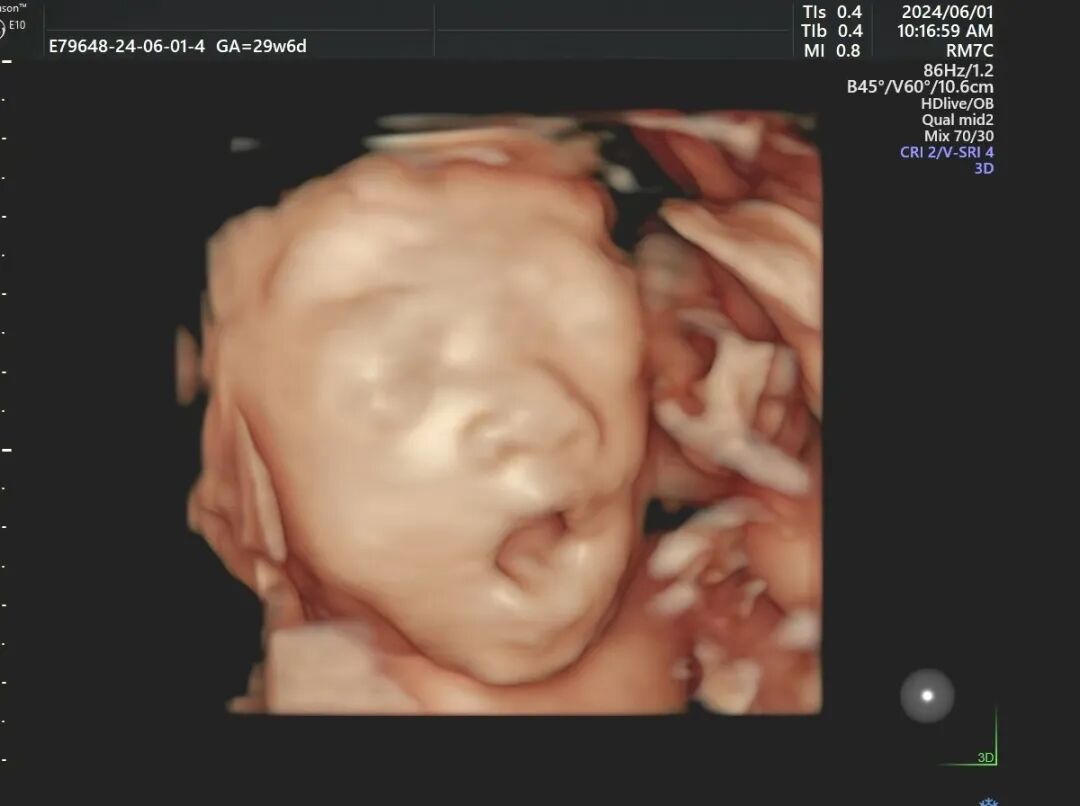

这次,宝宝好像听懂话了,终于把正脸转过来了,TA长得跟小叶可真像~望着墙上的图像,小叶很激动,这一刻,她感觉辛苦都是值得的。

只见医生眼疾手快地在屏幕上不停截屏,测量股骨、双顶径,切换到一个红蓝色的界面时,小叶老公好奇地问医生,“医生,这是什么?”

“这是心脏血流,红蓝色块代表血管内红细胞的流动方向,我们根据血流方向来判断心脏血流供应情况”,医生又切换了一个图像,“这里是脐带的血流,能看到有明显的红色和蓝色,我们通过这些图像,可以直观地做诊断。”

“我们医院采用的设备是四维E10,清晰度、性能上更强,能实时捕捉宝宝的动态画面,显示出胎儿的颜色、面、各器官,发现胎儿畸形、唇裂、腭裂、骨骼发育异常等;还有胎儿的心脏、脐带、血流变化、中枢系统及脊柱等,提供更精准、更直观的图像。”医生介绍道。

医生看过小叶的四维报告,开心地说:“小宝贝的数据不错哟~”这一句话,化解了小叶今天所有的忐忑。